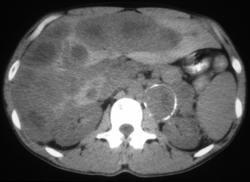

问题 男,37岁,阵发性高血压1月余,请结合所提供图像,选择最佳答案()

选项 A.左侧肾上腺癌 B.左侧恶性嗜铬细胞瘤 C.左侧肾上腺转移瘤 D.肝转移瘤 E.原发性肝癌

答案 BD